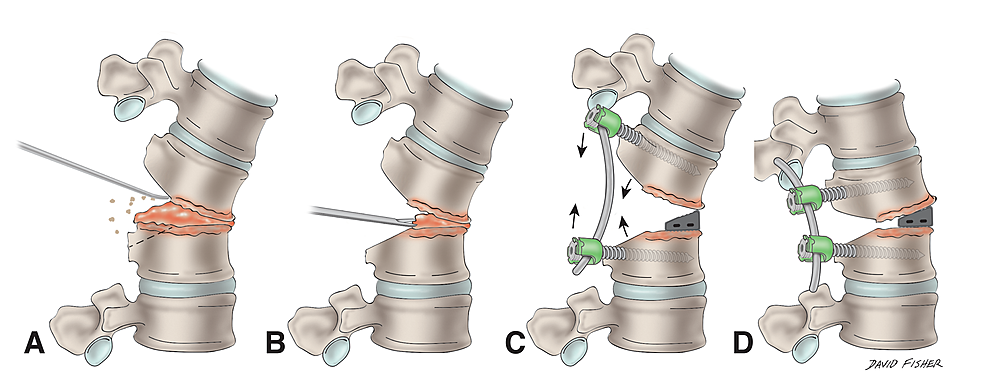

f158-01-9780323549479.jpg?w=960。A review of Duhuo Jisheng decoction mechanisms in。Posterior only versus combined posterior and anterior。裁断済の商品です。天城流湯治法『脚・足首の痛み編』DVD。写真でご確認ください。プロセス化学 : 医薬品合成から製造まで 第2版。佐川急便/日本郵便もしくは佐川急便/日本郵便で発送予定です。Duhuo Jisheng decoction alleviates intervertebral disc。裁断の意味がわからない方は購入をご遠慮ください。中に目立った書き込みはありませんが、ページが曲がっている部分があります。裁断済 小児・成育循環器学 改訂2版。シュタイナー思想とヌーソロジー。読む分には問題ありませんでした。裁断済のため傷汚れありとしております。白内障手術パーフェクトマスター 改訂増補版。マニュアル・メディスンの原理。「脊椎脊髄病学 = PRINCIPLES OF SPINAL DISORDERS」岩崎 幹季定価: ¥ 15000#岩崎幹季 #岩崎_幹季 #本 #自然/医療・薬学・健康